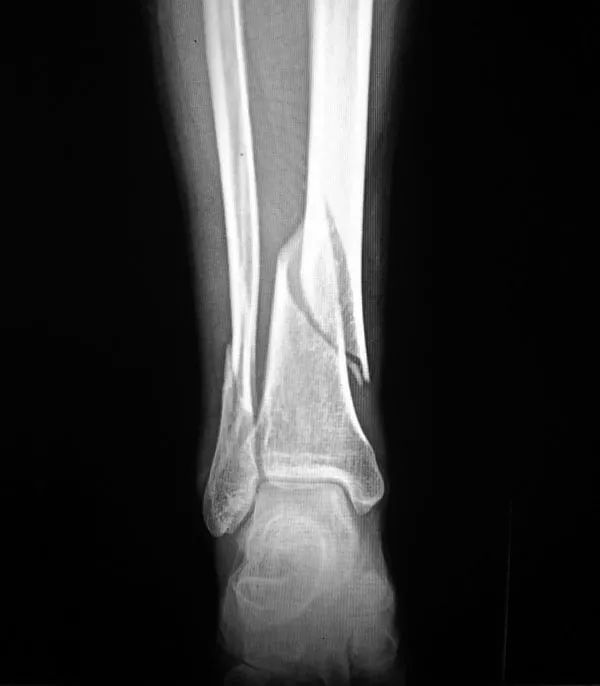

2、骨折骨質(zhì)疏松癥最常見的并發(fā)癥是骨折,輕微外力即可導(dǎo)致骨折,60歲以上老年人骨質(zhì)疏松并發(fā)骨折者高達(dá)12%。多見咳嗽打噴嚏時、彎腰屈伸撿東西、回頭轉(zhuǎn)身及摔倒等易發(fā)生骨折。骨量丟失20%以上時易發(fā)生骨折,輕者可使活動受限,重者須長期臥床,給社會和家人造成很大負(fù)擔(dān)。老年人骨折可引發(fā)或加重心腦血管并發(fā)癥,導(dǎo)致肺感染和褥瘡等多種并發(fā)癥的發(fā)生,嚴(yán)重危害老年人的身體健康,甚至危及生命,死亡率可達(dá)10%~20%。